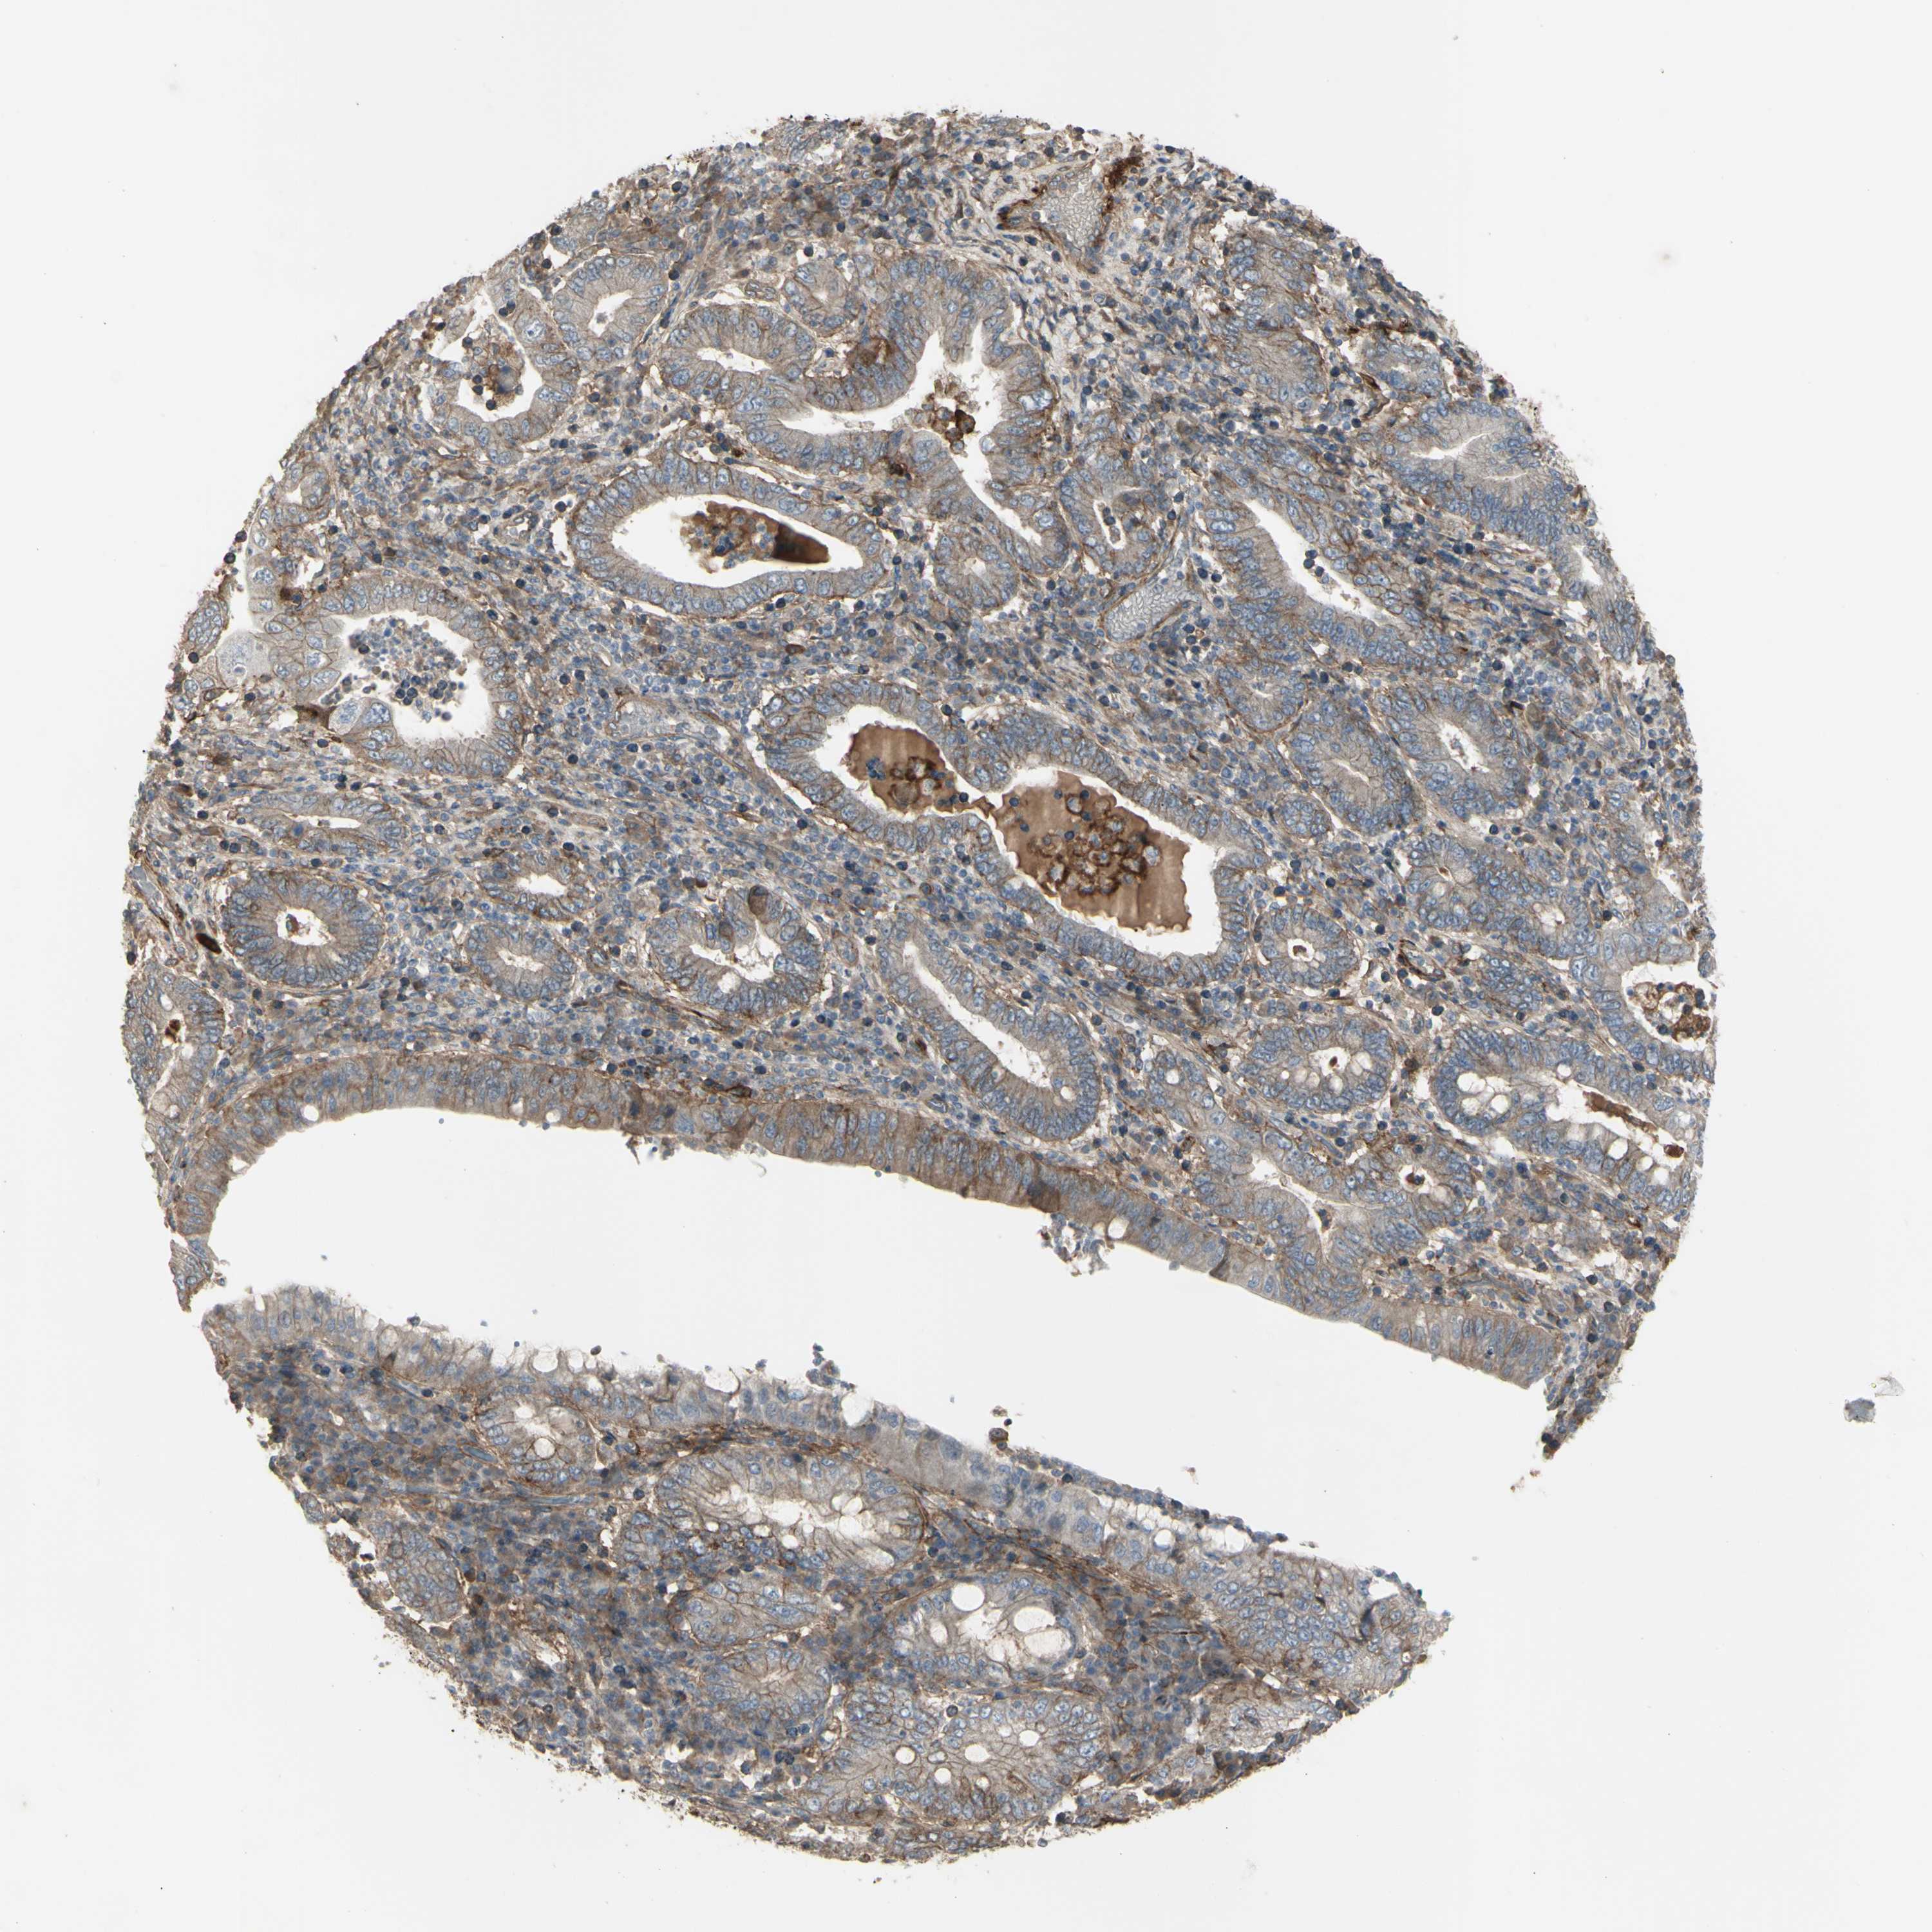

STOMACH CANCER - Protein expressioni

A mouse-over function shows sample information and annotation data. Click on an image to view it in a full screen mode. Samples can be filtered based on level of antibody staining by selecting one or several of the following categories: high, medium, low and not detected. The assay and annotation is described here.

Antibody stainingi

Antibody staining in the annotated cell types in the current human tissue is reported as not detected, low, medium, or high, based on conventional immunohistochemistry profiling in selected tissues. This score is based on the combination of the staining intensity and fraction of stained cells.

Each image is clickable and will lead to virtual microscopy that enables deeper exploration of all samples and also displays staining intensity scores, fraction scores and subcellular localization as well as patient and tissue information for each sample.

Antibody HPA009285

Antibody HPA017139

Antibody CAB017826

Staining

High

Medium

Low

Not detected

Intensity

Strong

Moderate

Weak

Negative

Quantity

>75%

75%-25%

<25%

None

Location

Nuclear

Cytoplasmic/membranous

Cytoplasmic/membranous,nuclear

Adenocarcinoma, NOS

Adenocarcinoma, High grade